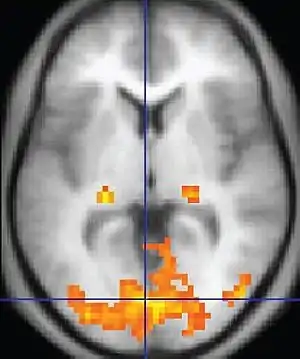

يستخدم الشكل الأولي للتصوير بالرنين المغناطيسي الوظيفي التباين المعتمد على مستوى الأكسجين في الدم (بي. أو. إل. دي)، الذي اكتشفه سيجي أوغاوا عام 1990. وهو نوع متخصص من فحص الجسم والمخ يستخدم لرسم خريطة للنشاط العصبي في المخ أو النخاع الشوكي للبشر أو الحيوانات الأخرى بتصوير التغير في تدفق الدم (استجابة حركة الدم) المرتبطة باستخدام خلايا المخ للطاقة.[4] منذ وقت مبكرٍ من تسعينيات القرن العشرين، هيمن التصوير بالرنين المغناطيسي الوظيفي على أبحاث رسم خرائط المخ لأنه لا يتطلب من المرضى أن يخضعوا للحقن أو الجراحة، أو يتناولوا موادًا، أو يتعرضوا للإشعاع المأين. كثيرًا ما يقاطع هذا القياس تشويش من مصادر مختلفة؛ وبالتالي، تُستخدم عملياتٍ إحصائيةٍ لاستخراج الإشارة الأساسية. يمكن تمثيل تنشيط المخ الناتج بيانيًا عن طريق الترميز اللوني لقوة التنشيط عبر المخ أو المنطقة المحددة التي تمت دراستها. يمكن لهذه التقنية أن تمركز النشاط في حدود ملليمترات، لكن باستخدام التقنيات القياسية، لفترة لا تزيد عن بضع ثوانٍ.[5] الطرق الأخرى للحصول على التباين هي وضع علامات شريانيةٍ دوارة وتصوير الانتشار بالرنين المغناطيسي. يشبه الإجراء الأخير التصوير بالرنين المغناطيسي الوظيفي للتباين المعتمد على مستوى الأكسجين في الدم (بي.أو.إل.دي.إف.إم.ر.آي) ولكنه يقدم تباينًا مستندًا إلى حجم انتشار جزيئات الماء في المخ.[6]

أصبح معروفًا منذ تسعينيات القرن التاسع عشر أن التغيرات في تدفق وأكسجة الدم في المخ (والمعروفة إجمالًا باسم حركة الدم) ترتبط ارتباطًا وثيقًا بالنشاط العصبي. عندما تصبح خلايا عصبية نشطة، يزداد تدفق الدم الموضعي إلى مناطق المخ تلك، ويحل الدم الغني بالأكسجين (المؤكسج) محل الدم الفقير بالأكسجين (غير المؤكسج) بعد حوالي ثانيتين. يرتفع هذا إلى الذروة لأكثر من 4-6 ثوان، قبل أن يعود إلى المستوى الأصلي (وعادة ما ينزلق لأقل من وضع انطلاقه قليلًا). يُحمل الأكسجين بواسطة جزيء الهيموغلوبين في خلايا الدم الحمراء. يكون الهيموغلوبين منزوع الأكسجين (دي.إتش.بي) مغناطيسيًا (شبه مغنطيسي) أكثر من الهيموغلوبين المؤكسد (إتش.بي)، والذي يكون عمليًا مقاومًا للمغناطيسية (غير مغناطيسي). يؤدي هذا الاختلاف إلى إشارة رنينٍ مغناطيسي محسنةٍ حيث يتداخل الدم غير المغناطيسي بشكل أقل مع إشارة الرنين المغناطيسي. يمكن تخطيط هذا التحسن لإظهار الخلايا العصبية النشطة في كل مرة.[9]